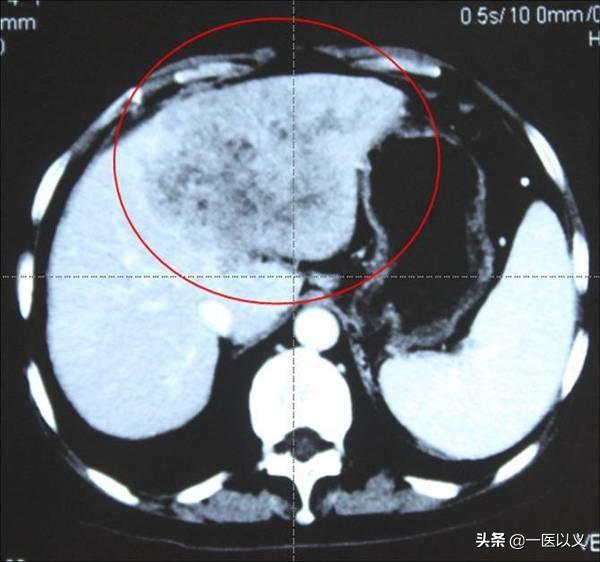

Le troisième.Imagerie du foie (CT, IRM)Ce test nous permet en outre de voir la forme du foie et de détecter les lésions antérieures du foie, de sorte qu'un résultat anormal au scanner peut ne pas refléter les lésions actuelles.

- Mais la tomodensitométrie hépatique a ses avantages : elle peut montrer la structure complète et les lésions du foie, ce qui n'est pas le cas de l'échographie hépatique.Si l'on prend l'exemple des tumeurs du foie, la tomodensitométrie du foie peut clairement montrer la localisation, la taille et la morphologie de la lésion, ce qui constitue dans une certaine mesure un guide pour le diagnostic et le traitement de la maladie. En outre, la tomodensitométrie améliorée du foie est très utile pour le diagnostic différentiel des maladies tumorales du foie et permet de distinguer le cancer du foie, l'hémangiome hépatique, les kystes hépatiques et d'autres maladies.

3. tomodensitométrie abdominale

En raison du niveau de lecture des films et des conditions d'équipement dans les hôpitaux de soins primaires, la tomodensitométrie de l'abdomen est plus souvent pratiquée que la résonance magnétique (RM). Pour le foie, la tomodensitométrie simple (sans contraste) ne permet d'examiner que les kystes hépatiques, les abcès hépatiques, les calculs intrahépatiques, etc. Pour aller plus loin et déterminer la nature de la masse hépatique, il est nécessaire d'effectuer une tomodensitométrie améliorée. C'est très simple : la tomodensitométrie améliorée est un examen au cours duquel un produit de contraste est injecté dans un vaisseau sanguin du bras, et le produit de contraste se déplace dans les artères et les veines jusqu'au foie pour développer une image. Le film scanné peut être comparé au film ordinaire et, dans la plupart des cas, il montrera la nature de la masse hépatique.

Le scanner amélioré est plus coûteux, mais je ne suis toujours pas sûr à 100 % de la nature de la masse hépatique. Un test est présenté ci-dessous.